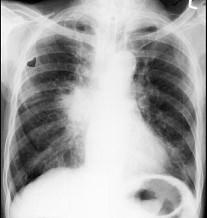

72岁,男,呼吸急促、气喘4个月,请结合胸片,选出最可能的诊断 ( )A.肺癌B.错构瘤C.肺结核D.韦格肉芽肿E.支气管腺瘤

问题 72岁,男,呼吸急促、气喘4个月,请结合胸片,选出最可能的诊断 ( )

选项 A.肺癌 B.错构瘤 C.肺结核 D.韦格肉芽肿 E.支气管腺瘤

答案 A